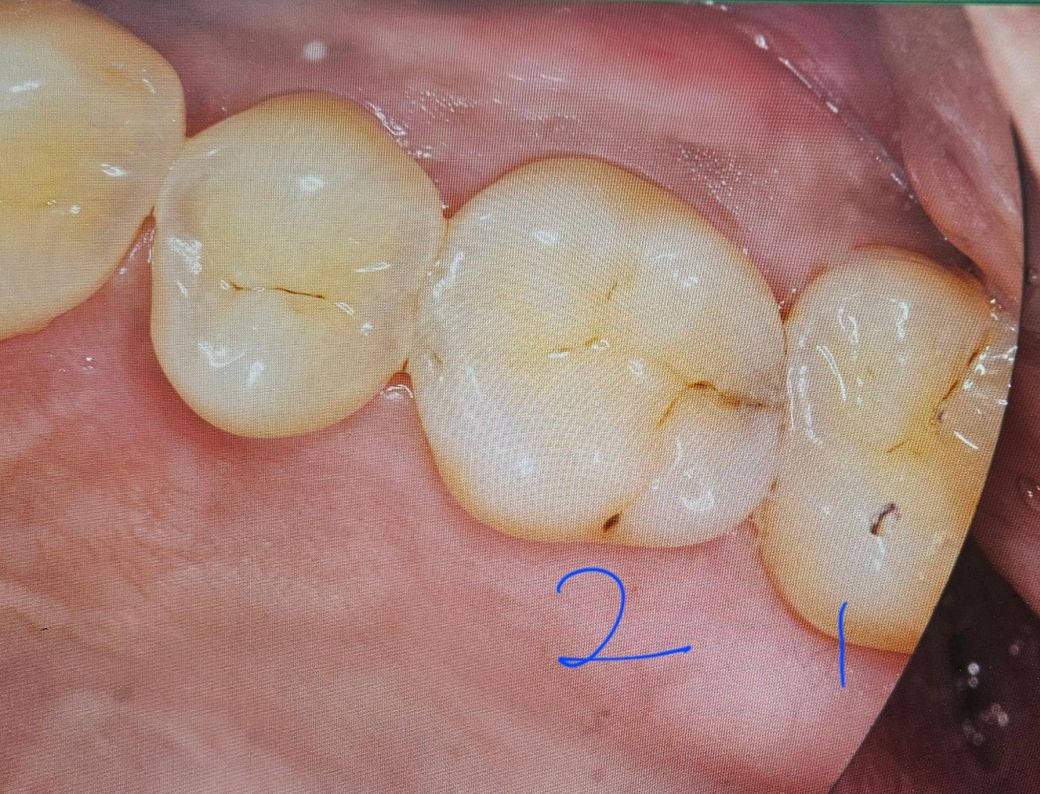

엑스레이와 사진찍어 보여 주시면서 사진상 1번과 2번이 만나는 부분에 충치가 있다고 하셨습니다.

간호사분 말씀으로는 사진상 1번과 2번 만나는곳이 조금 꺼멓다하시는데, 사진상 그렇게 보이시는지요?

• 1번 째 사진

사진으로 봤을 경우에 인접면에 충치가 보이기는 하지만 방사선 사진상에는 큰 충치가 보이지 않습니다. 따라서 많이 진행이 되지는 않은것으로 보입니다.

육안상으로 보면 충치가 치아 사이에 있는거 같습니다. 치료를 하시는게 좋을것같습니다.

네 육안사진상 인접면 충치 있어보입니다 엑스레이는 파노라마 보다는 치근단을 치아끼리 겹치지 않게 찍어봐야합니다